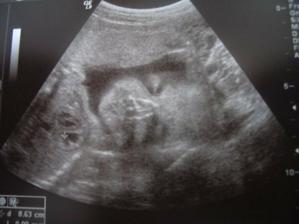

Dne 3.4.2007 to vypadá dle testů, že to vyšlo a my se snad dočkáme našeho vytouženého miminka a já nikdy nezapomenu děkovat a vážit si práce všeho personálu CAR u Apolináře. Dne 19.4.2007 nám bylo v CAR ultrazvukem potvrzeno, že opravdu čekáme naše vytoužené miminko. Dne 4.6.2007 jsme byli na genetickém UTZ ve 12+4.tt a UTZ dopadl na 1*. Dnes 26.7.2007 jsme byli na 3. ultrazvuku, jsme ve 20+2.tt a miminko je v naprostém pořádku. S maminkou už je to horši, ale snad všechno nakonec dobře dopadne. Dne 30.8.2007 jsme byli neplánovaně na 4. ultrazvuku a monitoru, protože maminka upadla na schodech, naštěstí je miminko v pořádku a neutrpělo žádnou újmu. Dnes 9.9.2007 jsme byli s tatínkem na 4D ultrazvuku v Gennetu Praha, máme krásné fotečky a DVD. Dozvěděli jsme se, že miminko v mém bříšku je holčička. Večer 9.9.2007 jsme naší holčičce vybrali jméno, je to Verunka.